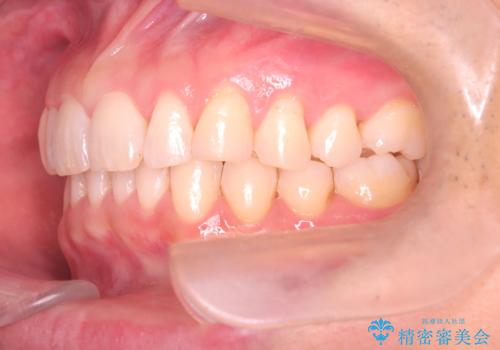

【インザライン】前歯の凸凹を治したい

- 前歯の凸凹を主訴に来院されました。

下顎位が右方に変異しており、外科矯正も提案しましたが患者様は希望されず、インビザラインにて治療を完了しております。

叢生のスペースを確保するために、臼歯部の遠心移動を行っています。

今回の治療計画は上顎の正中を顔と揃えることを優先しています。